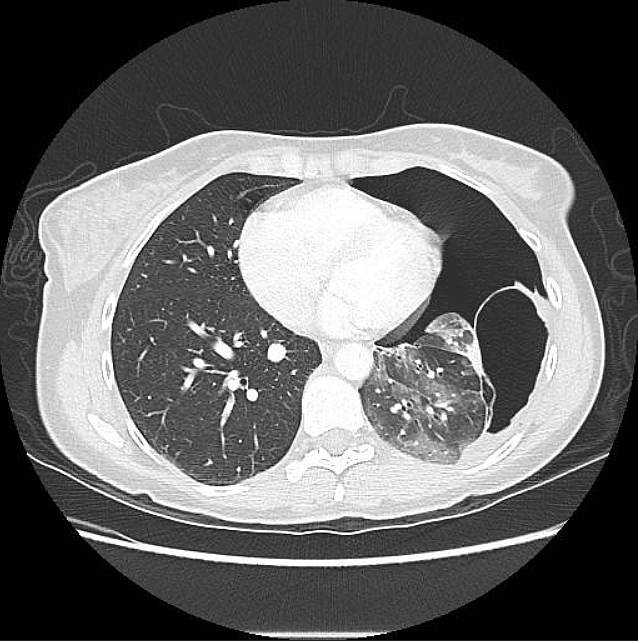

A contrast-enhanced CT of the thorax was then performed and revealed a moderately sized left-sided pneumothorax and a well-defined, thick-walled air-filled structure arising from the left lower lobe and adherent to the parietal pleura (image below).

Appearances on imaging vary depending on the contents of the cyst whether it be fluid, air or a combination of both. CT imaging findings are characteristically of a well-circumscribed round or ovoid solitary lesion with uniform fluid attenuation on CT [7] although the attenuation value can vary with the amount of proteinaceous content.

With the administration of IV contrast a non-enhancing or minimally enhancing thin wall is typically seen and the wall can calcify. Thick enhancing walls, septations, solid components and internal calcifications are not typically demonstrated [8].A definitive diagnosis of a bronchogenic cyst is made when respiratory epithelium is histologically present.